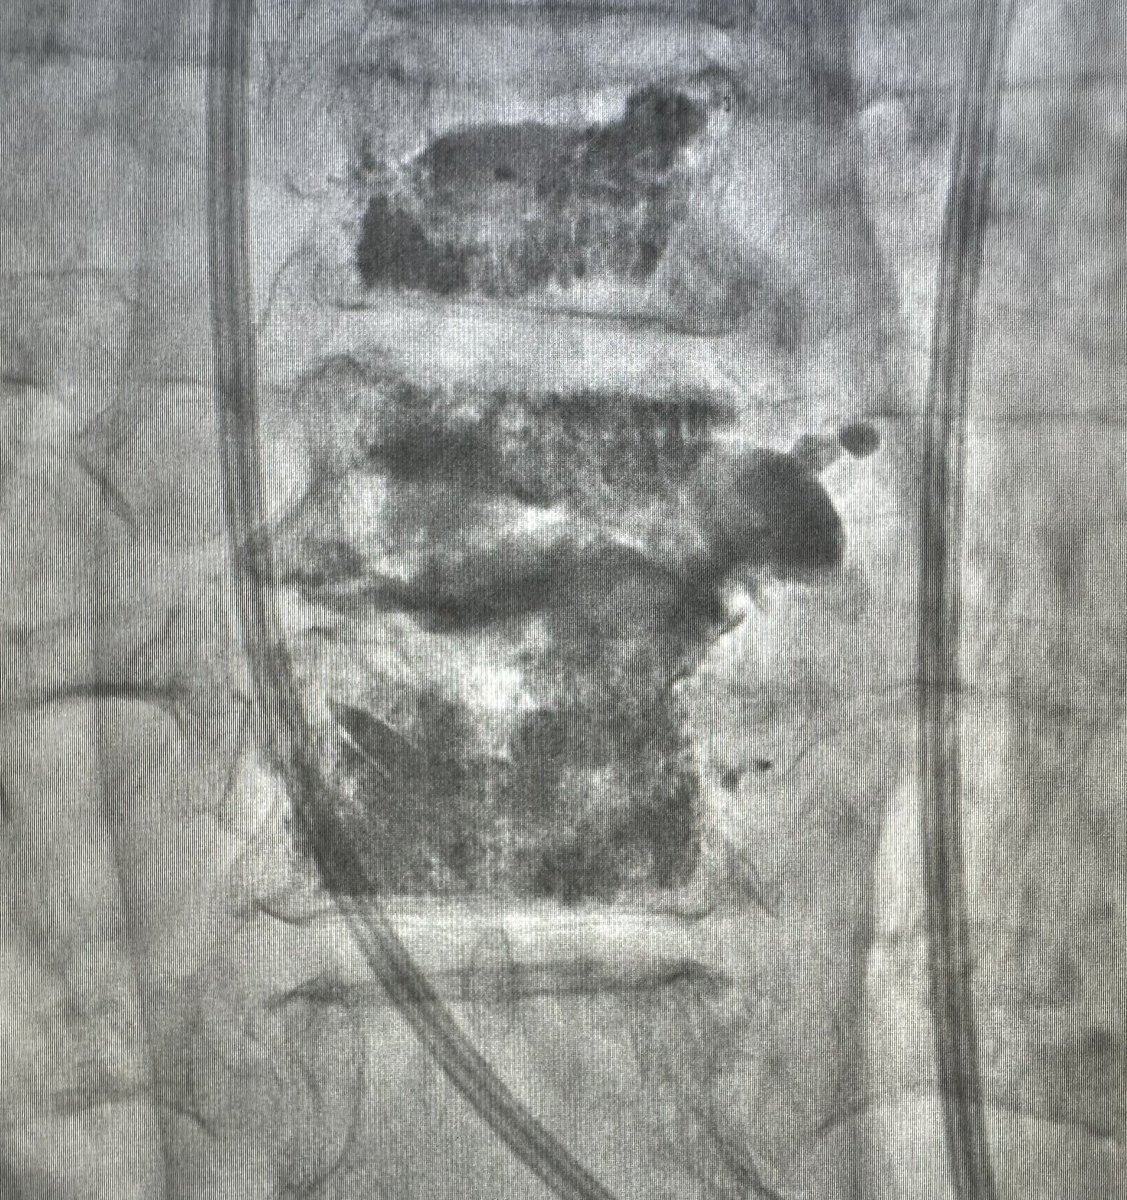

Sometimes controlled extravasation is beneficial. T10 and recurrent T9 fracture s/p T8,9 kypho previously. Fracture morphology complicated by DISH. Transpedicular disc access for T9 kypho and discoplasty to consolidate osteophyte and endplate. Ugly, but effective. #disasterplasty

(1/) Left parapedicular/costovertebral access to center of T10, right transpedicular access with cranial trajectory to T9-10 disc space and T9 inf endplate. T10 balloon faced pressure from the sclerotic but unhealed endplate.

(2/) Release the curette!

(3/) After initial cement from these accesses, the air filled fracture clefts are filled, but right side T10 is bare. Osteophyte blob = 👍🏼 Old accesses removed, new right transpedicular access with standard craniocaudal angulation. Moar curette. Curette = 🐐

(4/4) A bit more cement and done. The main principle for treatment of hinge-fractures (DISH, ank spond) is stabilization, primarily from compressive forces. Cement from top of T9 to bottom of T10 accomplishes this. Close follow-up to ensure stability and tx add'l fractures.